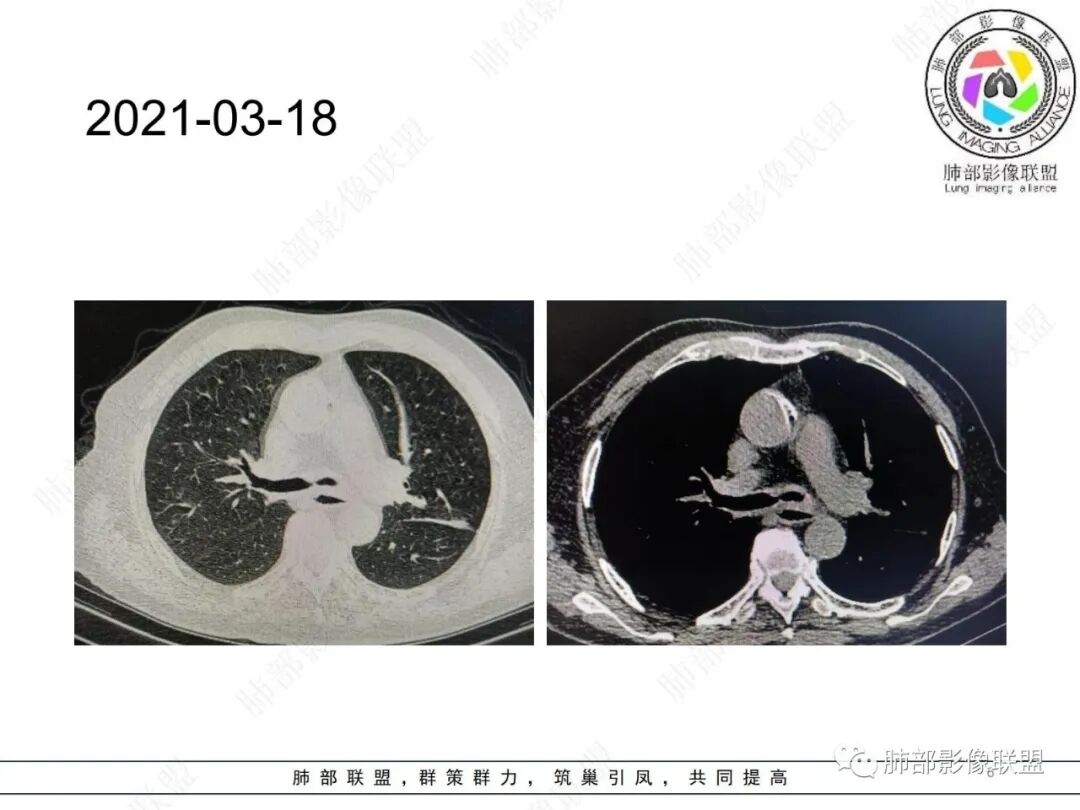

3/18:左主支气管壁弥漫增厚

补充视频:2021年3月17日

复查时间:2021年8月11日

病人当时住院抗感染治疗后症状有改善,没有进行其他化验检查,嘱咐3月后复查。病人直到喘的厉害才复查。

前后5个月左主支气管壁进行对称增厚及塌陷狭窄(解释咳喘加重),左侧胸廊变窄,左肺叶体积缩小,有实质和间质混合病变,向外周间质引流特点。复查右肺上尖后段多发小树丫及融合特点,TB?支气管镜活检。